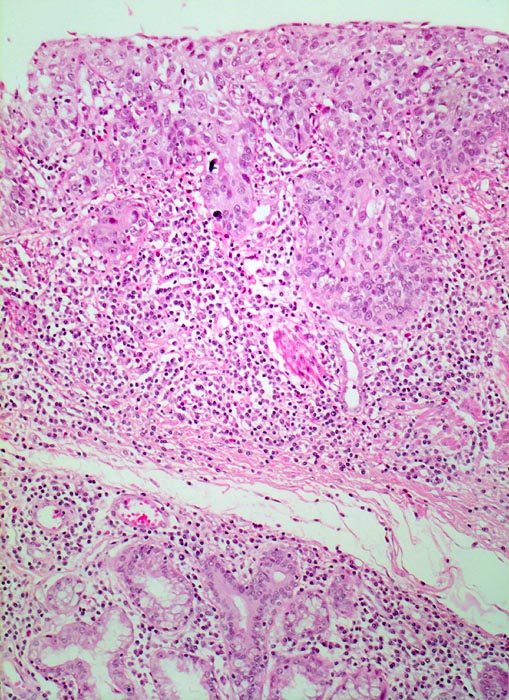

Mikroskopisch zeigen die meisten Plattenepithelkarzinome einen mittleren Differenzierungsgrad und eine wechselnd starke Verhornung. Das fortgeschrittene Karzinom infiltriert angrenzende Strukturen wie den Tracheobronchialbaum, die Aorta und den Nervus recurrens.

• Polypoides exophytisches Karzinom.

• Tumordurchbruch durch die Lamina muscularis mucosae in die Submukosa.

• Der Tumor bildet anastomosierende solide Zellstränge, die fokal im Zentrum verhornen.

• Tumorzellen mit reichlich glasigem eosinophilem Zytoplasma und scharfen Zellgrenzen mit stachelförmigen Interzellularbrücken. Stark vergrösserte, pleomorphe, hyperchromatische Zellkerne mit prominenten Nukleolen.

• Zwischen den Tumorzellsträngen desmoplastisches Stroma mit dichtem gemischtem Entzündungsinfiltrat.

• Präneoplastisch veränderte Mukosa im Randbereich des Karzinoms mit ausgeprägten Zellatypien in der gesamten Epithelbreite und zahlreichen Mitosen (Carcinoma in situ).